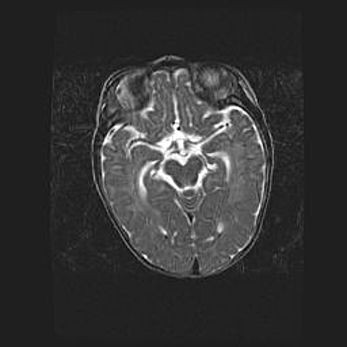

Церебральная ишемия II.

Возраст: 5 дней

Вес: 3400 г

Пол: женский

Окружность головы: 35 см

Срок гестации: 39 недель

Церебральная ишемия – это заболевание, характеризующееся недостаточностью (гипоксией) либо полным прекращением (аноксией) снабжения мозга кислородом по причине закупорки одного или нескольких сосудов. Это приводит к  что метаболическим расстройствам различной степени тяжести в тканях головного мозга, развитию коагуляционных некрозов и гибели нейронов.